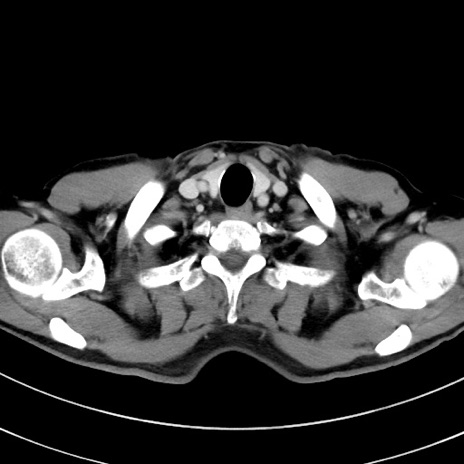

症例8(横断像)

【症例】 60歳代男性

【主訴】 黒色吐物

【現病歴】 4日前から嘔気自覚、2日前の朝食後にも嘔気あり、自分で手で嘔吐反射起こし嘔吐したところ血が混ざっていたため受診。

【既往歴】 5年前汎発性腹膜炎を伴う急性虫垂炎で手術、高血圧、前立腺肥大症、高脂血症

【身体所見】 腹部正中に手術癩痕あり 腹部平坦・軟圧痛なし膨満感あり

【データ】WBC 8400、CRP 4.54